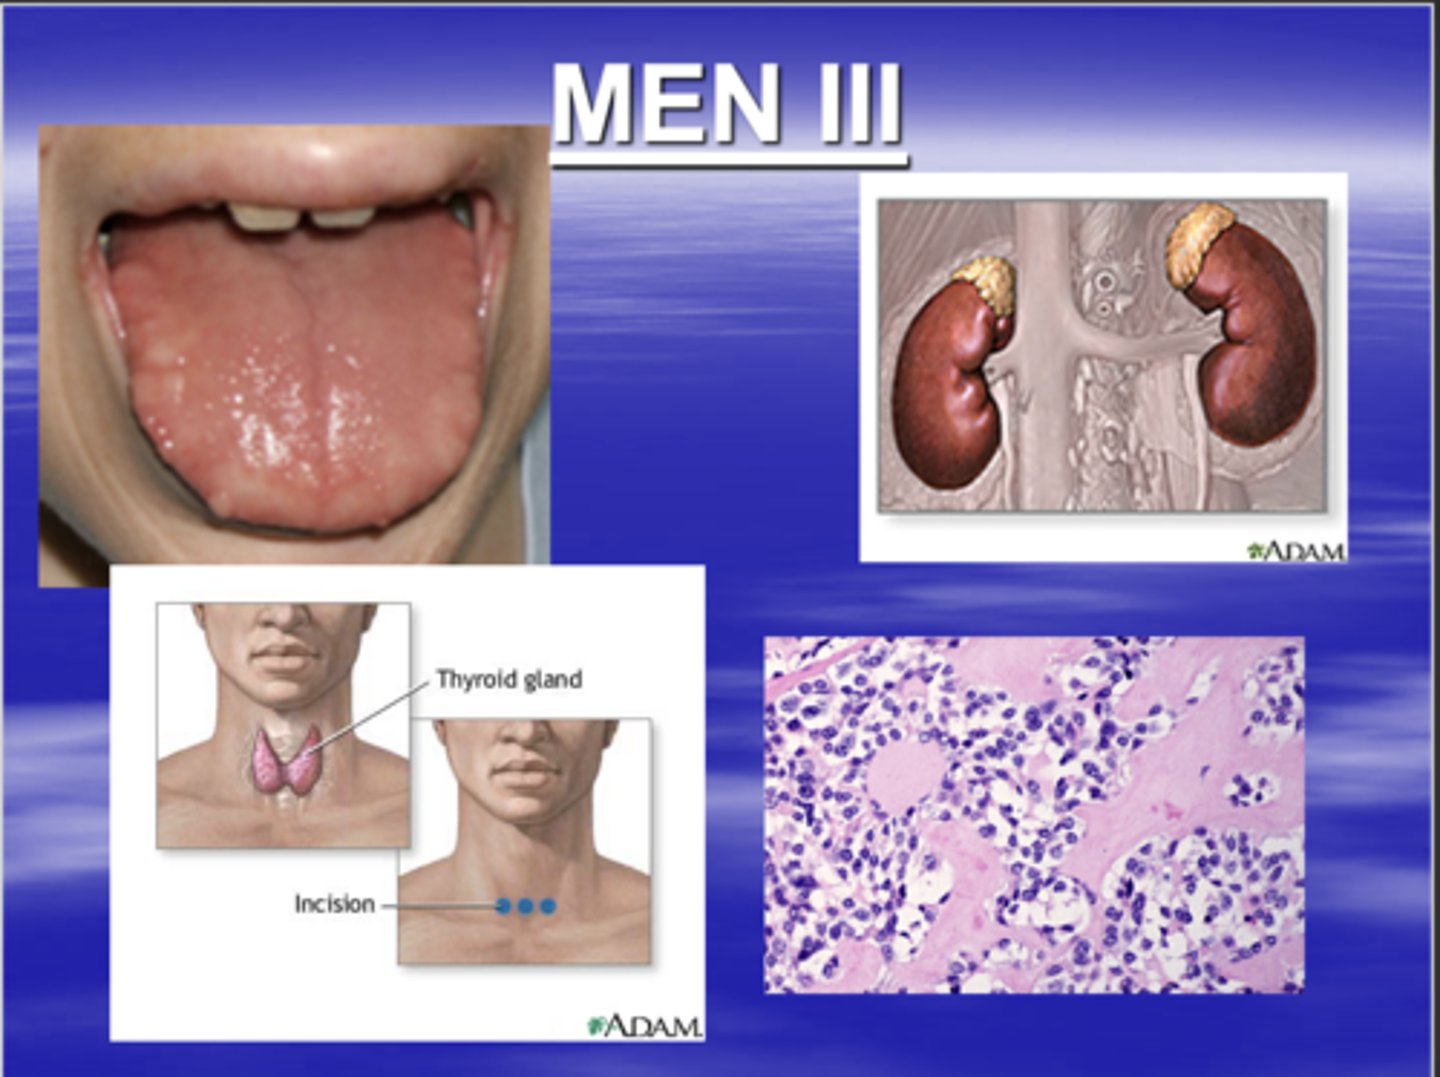

what is multiple endocrine neoplasia syndrome III? (MEN III)

characterized by:

1. multiple neuromas

2. pheochromocytoma

3. medullary carcinoma of the thyroid

you can save a patients life if you detect this